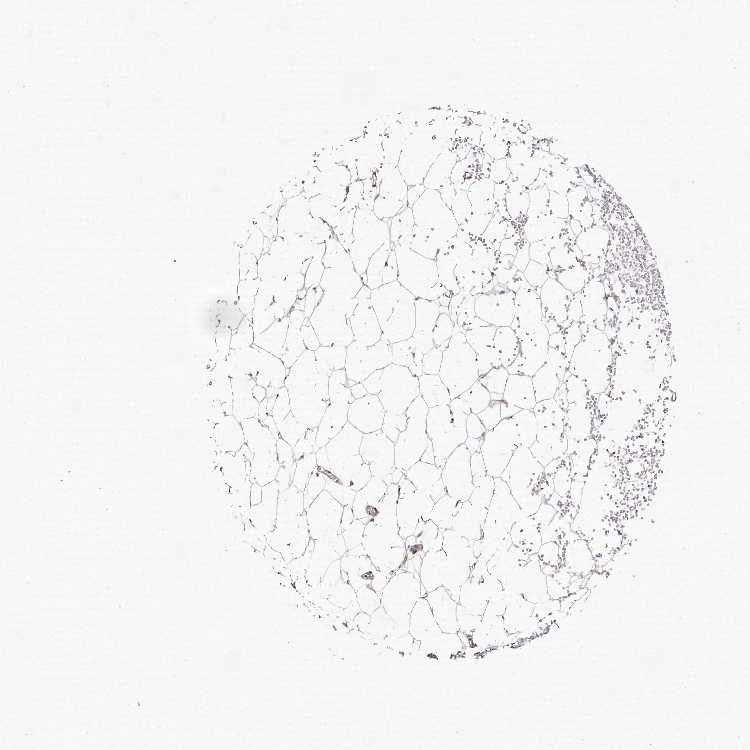

ADIPOSE TISSUE - Antibody stainingi

Antibody staining in the annotated cell types in the current human tissue is reported as not detected, low, medium, or high, based on conventional immunohistochemistry profiling in selected tissues. This score is based on the combination of the staining intensity and fraction of stained cells.

Each image is clickable and will lead to virtual microscopy that enables deeper exploration of all samples and also displays staining intensity scores, fraction scores and subcellular localization as well as patient and tissue information for each sample.

Antibody HPA028325Antibody HPA028435Antibody HPA030097

Adipocytes Not detectedNot detectedNot detected